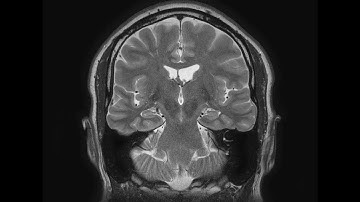

Accurate Estimation of TIV in MRI using a Multi-tasked Image-to-Image Translation Network